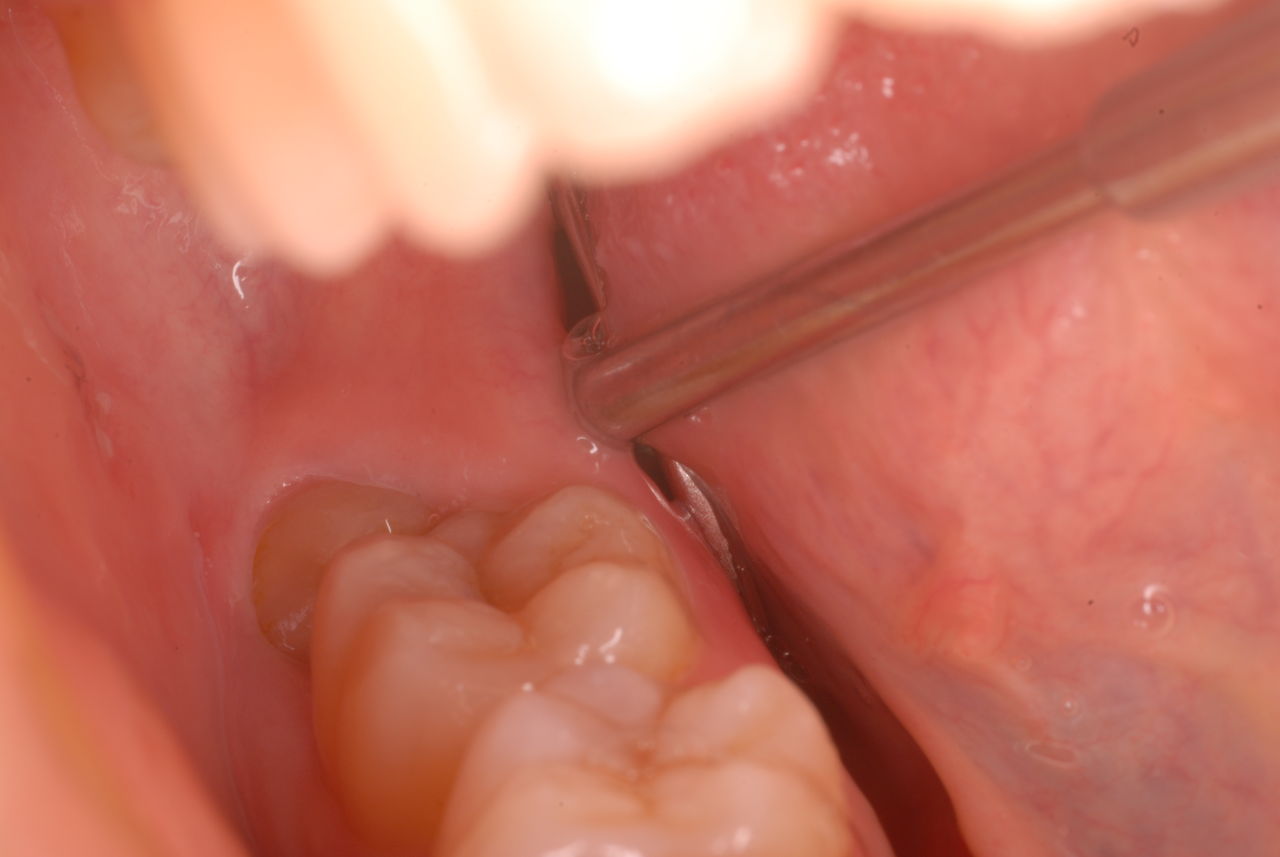

²¼³Ü²£¸þ¤¤Î¿ÆÉÔÃΤòºòÆüÈ´»õ¤·¤¿Êý¤ÎËÜÆü¤Î¾õÂ֤Ǥ¹¡£

Äˤߤâ¼ð¤ì¤â¤Ê¤¤¾õÂ֤Ǥ¹¡£Ë¥¤Ã¤Æ¤¤¤Ê¤¤¤Î¤ÇÈ´¤¤¤¿½ê¤ÏϪ½Ð¤·¤Æ¤¤¤Þ¤¹¡£¤À¤«¤é¤³¤½¼ð¤ì¤Ê¤¤¤Î¤Ç¤¹¤Í¡£Ë¥¹ç¤¹¤ë¤ÈÆâ½Ð·ì¤·¤Æ¼ð¤ì¤ë¤Î¤Ç¤¹¡£

»Äǰ¤Ê¤³¤È¤Ë½ý¸ý¤Ï³«¤¤¤Æ¤¤¤Þ¤·¤¿¡£